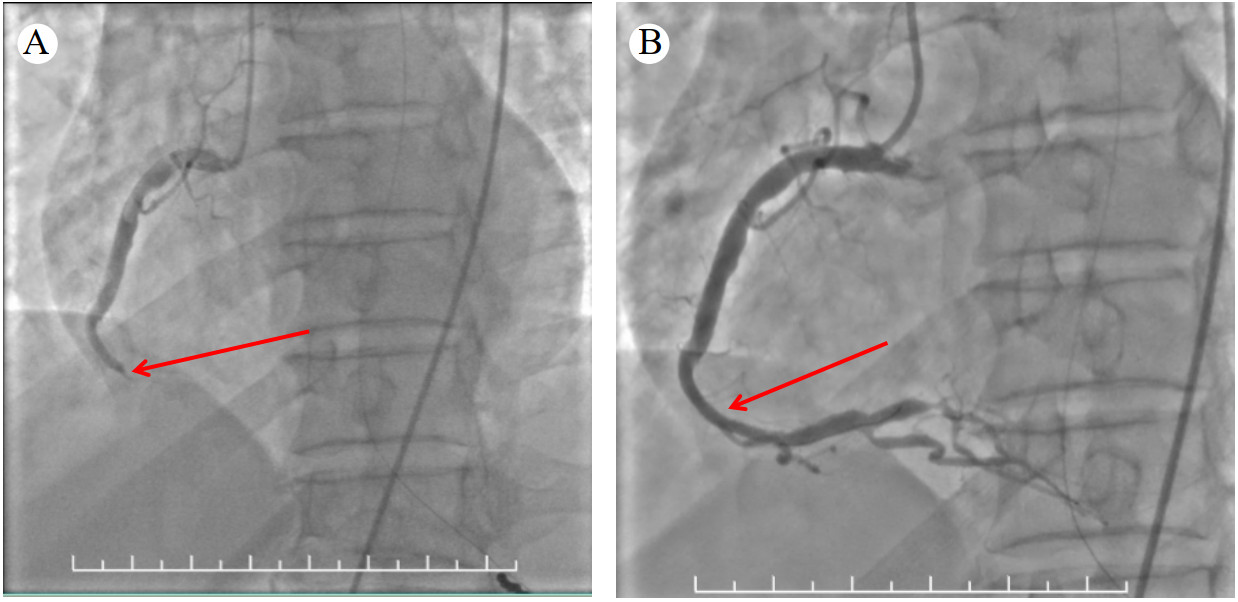

经多学科会诊决定在全麻下行急诊冠脉造影+冠状动脉介入术+脑血管造影+颅内动脉取栓术。手术开始时间为17:15,冠脉再通时间为17:22,脑血管再通时间为18:17。冠脉造影结果(图 3A):右冠近段瘤样扩张,中段闭塞,血栓负荷重,左前降支、左回旋支正常,未见右冠侧枝。给予肝素10 000单位,冠脉内血栓抽吸术后复查造影发现右冠几乎全程扩张,中段约30 mm为非扩张段,但此处急性闭塞,于右冠中段植入乐普2.5 mm×18.0 mm支架,效果满意(图 3B)。脑血管造影结果(图 4A):右侧颈内动脉末端闭塞,予取栓后血管再通(图 4B)。18:50患者转至重症医学科诊治。经鼻饲予氯吡格雷75 mg 1次/d、阿司匹林100 mg 1次/d、瑞舒伐他汀10 mg 1次/d,甘露醇125 mL静脉静注q 12 h等治疗,同时予脑保护、营养神经、维持内环境稳定等处理。

| 注:A为红色箭头为右冠闭塞处,右冠中、远端无血流;B为右冠支架(红色箭头处)植入后,右冠中、远端血流恢复 图 3 患者右冠状动脉造影 |